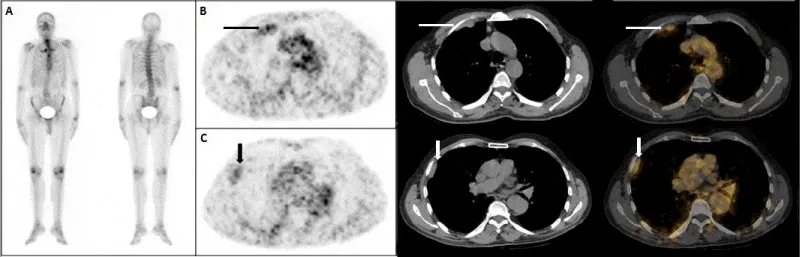

A 72-Year-Old man with newly diagnosed prostate cancer (PSA:12.47ng/ml, Gleason score:3+3) underwent skeletal scintigraphy before treatment. Suspicious Tc-99m MDP uptake was seen on right hemithorax (Figure 1A). Due to suspicious Tc-99m MDP uptake on right hemithorax on bone scintigraphy, further investigation using 68Ga-PSMA PET/CT was suggested. 68Ga-PSMA PET/CT revealed increased heterogeneous uptake in the right posterolateral segment of prostate gland compatible with prostate needle biopsy findings (adenocarcinoma). 68Ga-PSMA PET/CT images showed non-expected slightly increased uptake (SUVmax:1.6) in the right hemithorax greater than mediastinal blood pool activity (SUVmax:1.2), corresponding to pleural thickening seen on the CT images (first intercostals space (Figure 1B) and neighbourhood of the 4 and 6 rib (Figure 1C) with normal lung parenchyma. Thoracoscopic biopsy was performed to establish a definitive diagnosis. The results of histopathological examination (excisional biopsy) indicated the features of chronic inflammation with focal mesothelial hyperplasia. There was no evidence of stromal invasion.